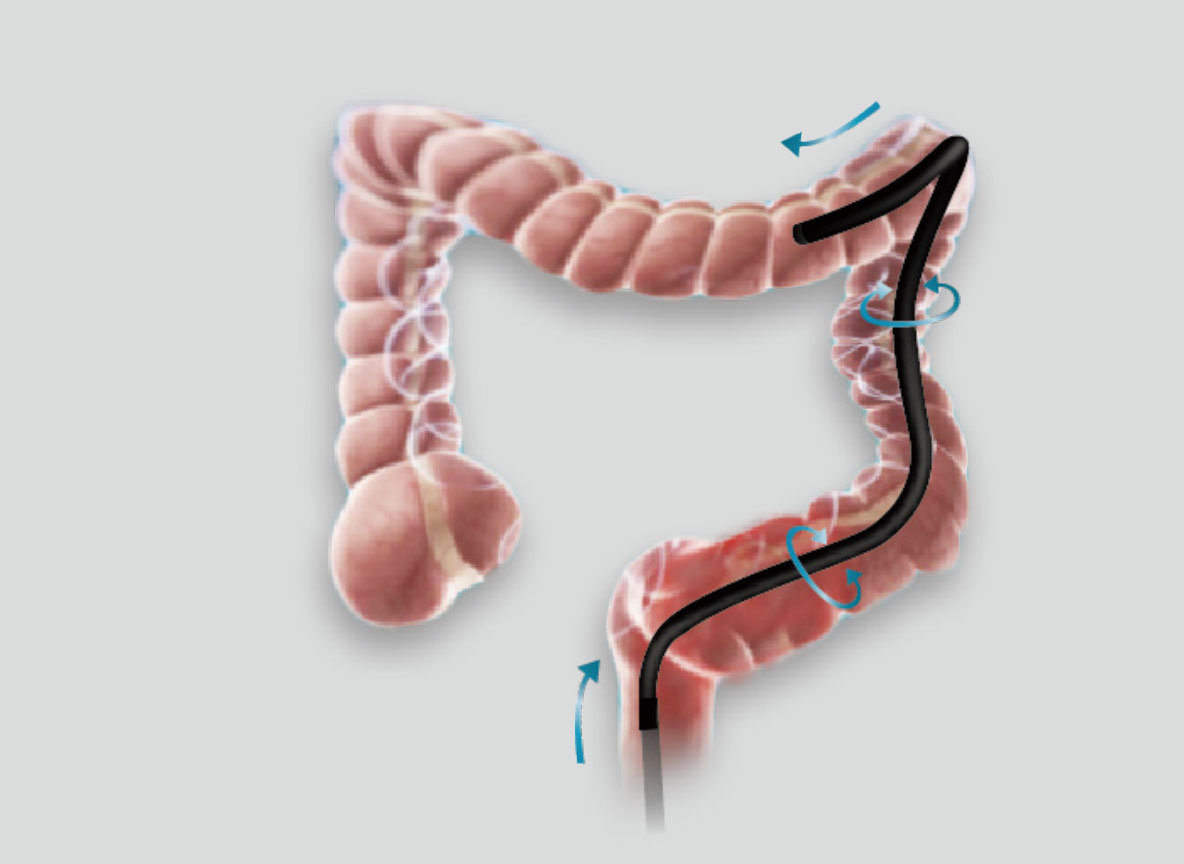

优秀的操控性和进镜性能

• 高传导性分段硬度插入设计

带来镜体插入及诊疗新体验。